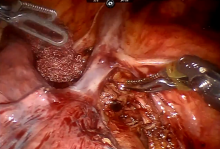

A variance from normal anatomy was discovered intraoperatively, in that the superior pulmonary vein could not be identified. An aberrant vein was subsequently discovered draining directly into the innominate vein. This anatomical variance was not picked up on in the preoperative computed tomography scan. In this case, a 3D reconstruction of the pulmonary vasculature would have been particularly helpful. During the procedure, it was important to preserve the aberrant vein so as to not disturb the drainage of the remaining segments.

Having found one variance from normal anatomy, it was important to not miss any other potential variations. Intraoperative testing, of bronchi via inflation and vasculature via indocyanine green, was employed throughout the procedure to confirm anatomy and support decision making.